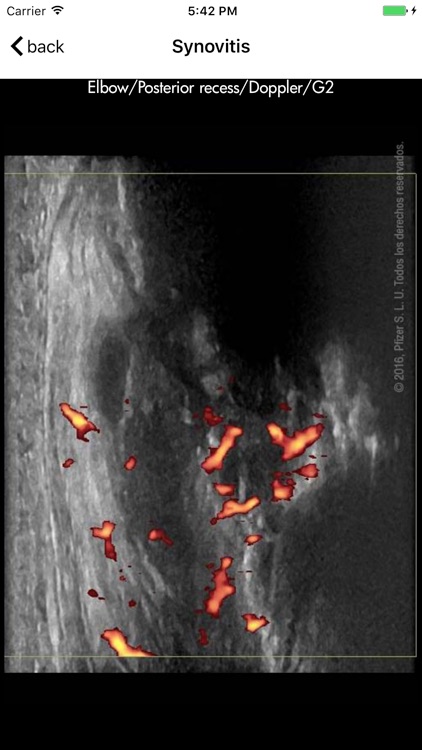

Ultrasound detected synovitis is a powerful imaging tool used worldwide that helps diagnose, monitor and treat patients with rheumatoid arthritis . RAUSSA application has been developed to help you score joint and tendon ultrasound grey scale and Doppler detected synovitis while performing your ultrasound examination. RAUSSA is made-up of almost 400 images from patients with rheumatoid arthritis. Takes no more than 2 minutes to learn! In every area you can look at a representative anatomic specimen image, up to 4 different US images with the same grey scale or Doppler mode score. , Dr. J. Uson MD PhD , Dr. I. Möller MD PhD and Dr. E. Naredo MD PhD, experts in rheumatologic ultrasound have obtained the images in this app.

Ultrasound detected synovitis is a powerful imaging tool used worldwide that helps diagnose, monitor and treat patients with rheumatoid arthritis . RAUSSA application has been developed to help you score joint and tendon ultrasound grey scale and Doppler detected synovitis while performing your ultrasound examination. RAUSSA is made-up of almost 400 images from patients with rheumatoid arthritis. Takes no more than 2 minutes to learn! In every area you can look at a representative anatomic specimen image, up to 4 different US images with the same grey scale or Doppler mode score. , Dr. J. Uson MD PhD , Dr. I. Möller MD PhD and Dr. E. Naredo MD PhD, experts in rheumatologic ultrasound have obtained the images in this app.

The ultrasound definitions and semi-quantitative scoring method used in this app. are those driven and reported by OMERACT (Outcome Measures in Rheumatology in Clinical Trials) validated for diagnoses and monitoring inflammatory activity in patients with rheumatoid arthritis (Bruyn GA, Naredo E, Iagnocco A. J Rheumatol 2015;42 (11):2172-6).